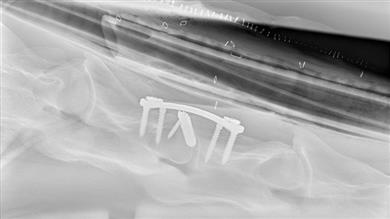

During surgery, the injured horse is anesthetized and placed in a surgical hammock to immobilize it. The fracture is stabilized with a 3D-printed plate and 3D-printed cancellous screws bridging the vertebrae, and depending on the case (and the vertebrae affected) with a small 3D-printed titanium cage applied in the ventral disc space. Cancellous or cortical screws may sometimes be associated with the locked screws to allow compression of the fractured fragment.

The benefit of this assembly lies in the fact that the 3D-printed titanium intervertebral spacer used during surgery makes use of compression forces to preserve the spacing between the vertebrae, thus preventing the protrusion of the disc in the medullary canal and the ventral displacement of the caudal vertebra.

The shape of the plate allows the placement of three screws in each vertebra. In addition, implants manufactured using titanium alloys have shown better osseointegration than steel implants. And unlike conventional machining, metal 3D printing allows for the creation of porous patterns that facilitate the growth of bone through the cage and the fixation of the bone onto the cage.

Finally, the screws used are self-tapping and partially self-drilling, which allows maximum anchorage (close to the medullary canal) while reducing the risk of perforation during drilling or tapping. In Rossignol's experience, the use of a Redon drain limits this risk. Screw disinsertion or pullout may occur, but it is likely to be due to technical errors or associated with poor contact between the plate and the bone surface.